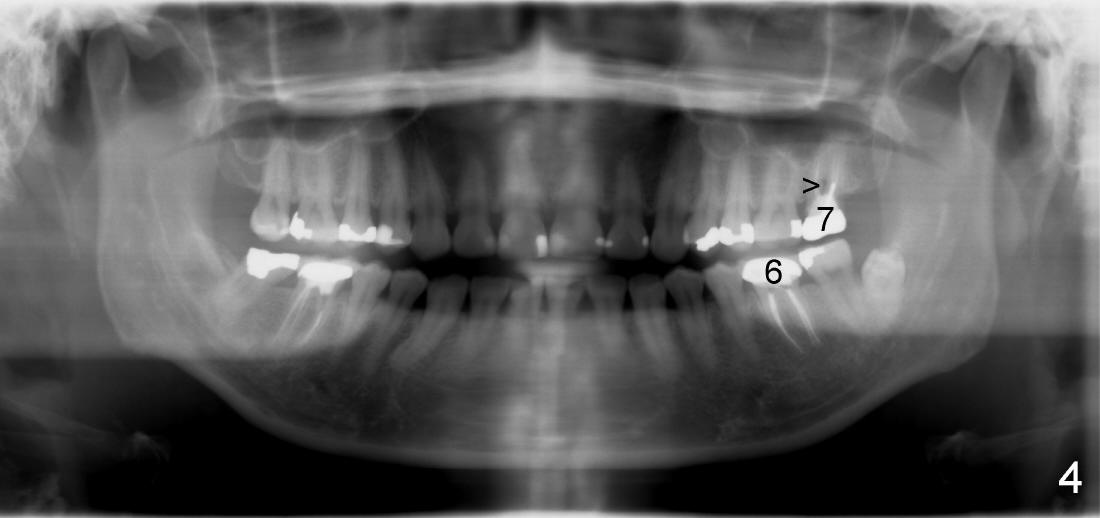

其实本文题目是如何让植牙病人找上门。冯女士四十二岁,四五年前因左下六牙痛第一次登门就诊,X光片显示牙根很长(图一),近中根根尖有阴影(>),那根牙根弯曲,总之,稀里糊涂开始根管治疗,结果有四根根管(图二),又长又弯,远中舌侧根断针(>),但是重新通过,辛辛苦苦完成根管治疗时才发现远中舌侧根弯弯曲曲(图三箭头,黑色箭头指向原来断针)。这些年来这颗牙齿没问题,但是左上七号牙老是发炎,全景片表明那颗牙齿根分叉处有阴影(图四箭头),一直劝她拔牙,植牙,上个月她终于同意拔牙,准备年底植牙。只有认认真真为病人解决痛苦,才能赢得他们信任,一旦他们需要进一步治疗,也会乐意开口。根管治疗做起来吃力,但是最能显示赤胆忠心。做好根管治疗是开展植牙第一步,愿意保留牙齿的人,视牙如金,如果我们尽力而保留不了,他们还是愿意更上一层楼;轻易拔牙的病人很少后来回来做植牙。